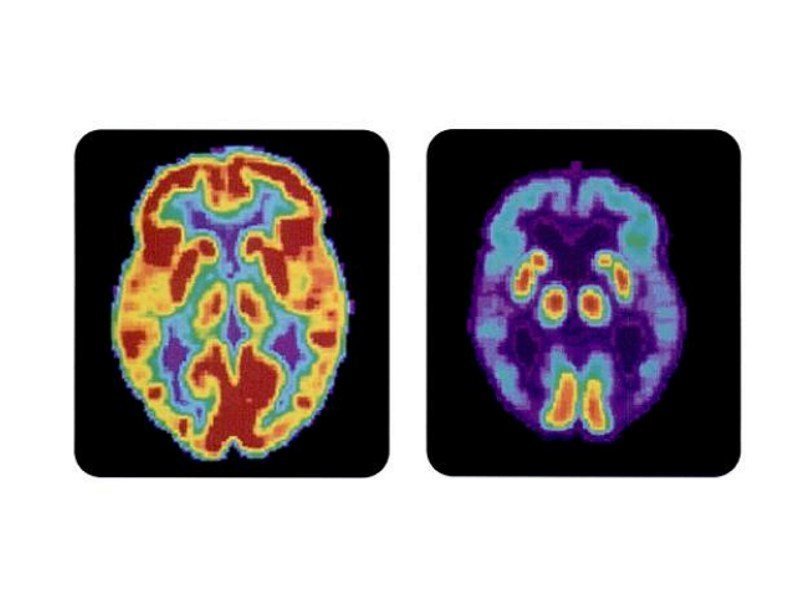

Томограмма здорового мозга и мозга пациента с болезнью Альцгеймера Wikimedia Commons Опубликованные недавно результаты клинических испытаний нового средства для лечения болезни Альцгеймера подтверждают давние подозрения врачей о том, что причиной заболевания оказывается белок бета-амилоид. Но для окончательного вывода данных, по мнению ученых, еще слишком мало.

В длившейся год фазе испытания участвовали 165 человек с умеренными когнитивными нарушениями или деменцией, вызванными болезнью Альцгеймера. Они принимали препарат в разных дозах (1, 3, 6 или 10 мг/кг) или же плацебо. После 54 недель позитронно-эмиссионная томография показала, что в мозге у тех, кто получал препарат, имелось меньше бета-амилодных отложений, чем у получавших плацебо. Причем, чем вышел была доза адуканумаба, тем ниже оказывался уровень бета-амилоида.